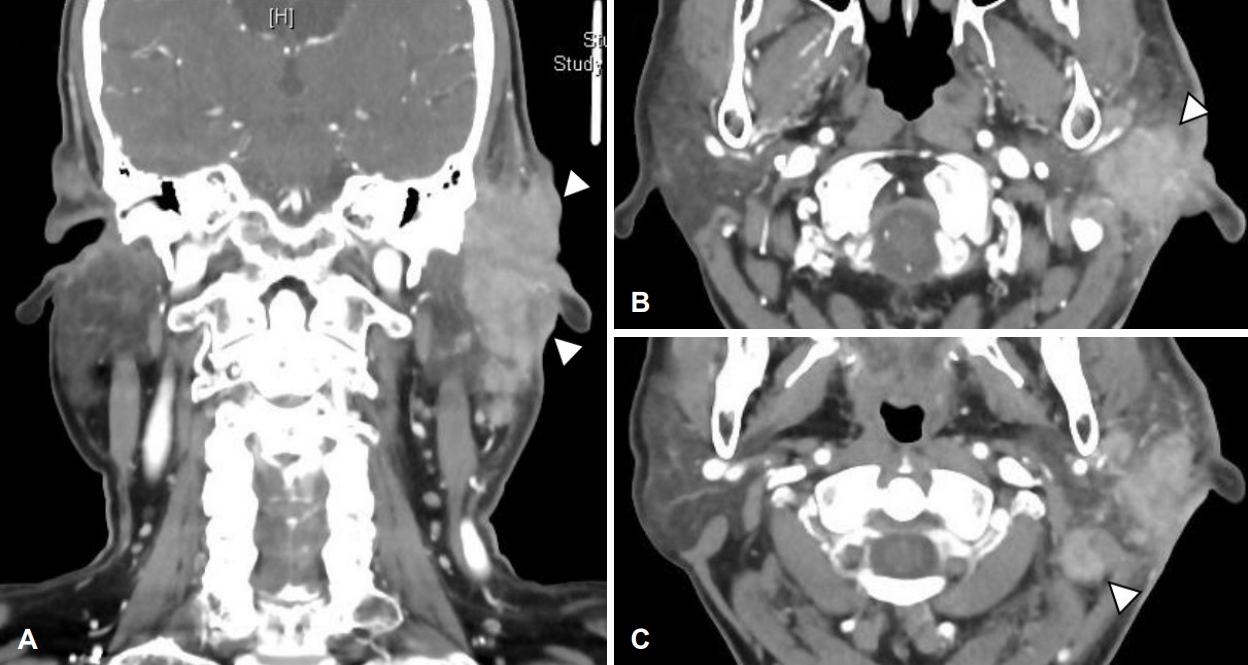

외이도 연조직염 진단하 경험적 경구 항생제 투약 및 병변 부위 드레싱을 1주 이상 시행하였으나, 외이도 부종 악화로 인한 외이도 연골부 협착 소견 및 장액 혈성 이루가 관찰되었다. 이에 치료 시작 후(post start of treatment day) 24일에 입원하여 이주 및 외이도의 염증성 조직에 대하여 정맥 항생제 치료 및 악성종양 의심하 조직 생검을 시행하였다(Fig. 2A and B). 경부 컴퓨터단층촬영상 좌측 외이도와 이개 주변 3.4×2.3×2.9 cm 크기의 병변과 이하선 하부로 타원형의 림프절 비대가 관찰되었다(Fig. 3). 조직 생검상 급성 및 만성 염증소견이 보고되었으며, 균 배양 검사 결과 메티실린 내성 황색포도상구균이 동정되어 vancomycin을 사용하며 보존적 치료를 시행하였다. 치료 초기에는 호전 양상을 보였으나 이후 다시 악화되는 양상이었다(Fig. 2C and D). 백혈구수치, 적혈구침강속도, C-반응성 단백질, 항핵항제, 류마티스 인자, IgG 등의 혈청검사상 정상 범위였으며, 단순 포진 바이러스 및 대상포진 바이러스에 대한 viral marker 검사에서 현성감염증 등의 특이소견은 보이지 않았다.

NotesAuthor Contribution Conceptualization: Tae Hoon Kong. Data curation: Dong Hwan Kwon. Funding acquisition: Tae Hoon Kong. Investigation: Minheon Kim. Project administration: Tae Hoon Kong. Supervision: Tae Hoon Kong. Visualization: Minheon Kim. Writing—original draft: Joo Hyung Lee. Writing—review & editing: Joo Hyung Lee, Tae Hoon Kong. Fig. 1.Initial ear findings and audiometry of the patient on first visit. A: Initial skin and soft tissue inflammation (post start of treatment day 21). B: Pure tone audiometry shows the air-bone gap (35 dB) of the left ear (red: right ear, blue: left ear). Fig. 2.Skin and soft tissue inflammation. Redness and swelling aggravated during antibiotic therapy and daily wound care. A: Post start of treatment day (PTD) 40. B: PTD 46. C: PTD 64. D: PTD 69. E: PTD 93. F: PTD 99. Fig. 3.CT of neck. 3.4×2.3×2.9 cm sized enhancing mass-like lesion at left external auditory canal and left ear auricle with enlarged lymph nodes at periparotid region. A: Coronal view. B: Axial view. C: Axial view of enlarged lymph node. Fig. 4.MRI of temporal bone. Subepithelial soft tissue thickening in the external auditory canal (cartilaginous portion) and auricle aggravated during antibiotic therapy and daily wound care. A: Post start of treatment day (PTD) 16, T2 weighted image (T2WI) axial. B: PTD 16, T1 weighted image (T1WI) coronal. C: PTD 96, T2WI axial. D: PTD 96, T1WI coronal. Fig. 5.PET-CT scan (torso). Left external auditory canal and left ear auricle, periauricular area, left parotid gland involving irregular hypermetabolic lesion was seen. Fig. 6.Histological findings. Polymorphous lymphoid cells infiltrate lacing cytologic atypia on PTD 112 compared to previous study. A: Post start of treatment day (PTD) 16, ear, Lt (hematoxylin and eosin [H&E], ×200). B: PTD 24, ear, Lt (H&E, ×200). C: PTD 58, parotid gland, Lt (H&E, ×200). D: PTD 112, ear, Lt (H&E, ×200). E: PTD 112, ear, Lt (CD3, ×100). F: PTD 112, ear, Lt (Epstein-Barr virus in situ hybridization, ×100 view). Fig. 7.Skin and soft issue inflammation has shown much improvement and epithelization of the wound was achieved after six months of treatment (post start of treatment day 174). Table 1.Differential diagnosis of chronic active Epstein-Barr virus of T-cell type REFERENCES1. Wauchope J, Dorris CB, Smith CP, Hanna B. Chronic active Epstein-Barr virus: A multidisciplinary approach. BMJ Case Rep 2020;13(12):e236287.